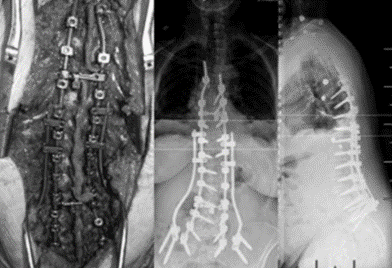

(4)Topping-Off 技术

Topping-off技术又称为融合区+上位邻近节段动态稳定技术

即从融合节段向活动节段过度的手术,旨在融合节段和活动节段之间形成缓冲区,降低邻近节段应力集中

图34-35 据文献报道,可应用一种环形和夹层胶带的技术,以重新创建一个有机后张力带UIV和UIV+1之间将上下棘突绑扎后,增强交界区后方张力带结构强度